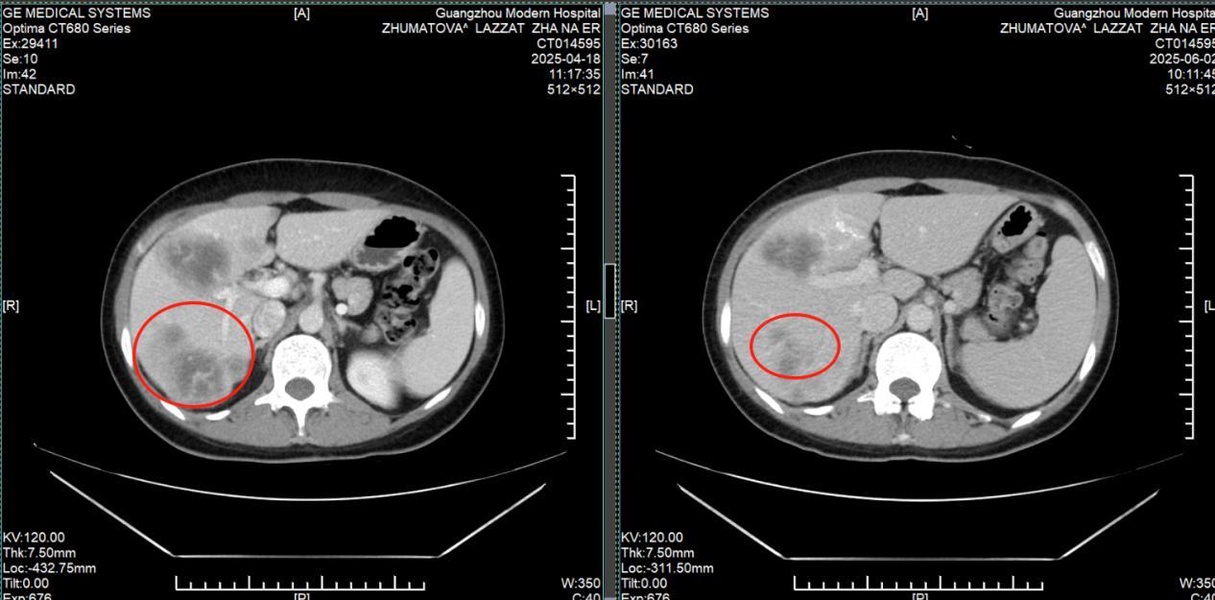

История пациента: Ляззат, 47 лет, юрист, Казахстан. Диагноз: Рак молочной железы IV стадии с множественными метастазами в печень. Тактика лечения: Комбинация интервенционной терапии (химиоэмболизация) и микроволновой абляции (МВА). Результат: Полная регрессия опухоли в молочной железе, уменьшение метастазов в печени более чем вдвое, нормализация функции печени и онкомаркеров. Неожиданная находка: когда привычный мир рухнул Ляззат - успешная женщина из Казахстана, юрист, привыкшая решать сложные задачи в суде, в начале 2025 года столкнулась с самым тяжелым делом в своей жизни. Обследование, начатое из-за усталости и скачков давления, привело к шокирующему открытию: во время УЗИ случайно обнаружили опухоль в печени, а вскоре она сама нащупала уплотнение в груди. Диагноз прозвучал как приговор: рак молочной железы IV стадии с множественными метастазами в печень. Местные врачи настаивали на единственном, по их мнению, варианте: длительном курсе химиотерапии и обязательной мастэктомии - удалении молочной железы. Принципиальное решение: сохранить не только жизнь, но и себя Для сильной и осознанной женщины это было неприемлемо. «Грудь - это не просто орган, это часть моей женской идентичности. Я никогда не соглашусь на ее удаление и должна найти лучшее решение», - так Ляззат сформулировала свою позицию. Она обратилась в клиники Турции, Индии, Южной Кореи, но нигде не получала гарантий, что лечение сможет победить рак и сохранить грудь. В момент отчаяния надежду подарила подруга, порекомендовавшая St.Stamford Modern Cancer Hospital Guangzhou и его малоинвазивные подходы.

Результат превзошел все ожидания. После двух курсов комбинированного лечения: • Опухоль в молочной железе полностью исчезла. • Метастатические очаги в печени уменьшились более чем в два раза. • Функция печени и уровень онкомаркеров (РЭА, СА153) пришли в норму. • Вернулись силы, ушла постоянная усталость. Уже в третий визит в Гуанчжоу Ляззат приехала одна, чувствуя себя настолько хорошо, что могла перенести длительный перелет и вернуться к привычной жизни. Ценить настоящее: урок, выученный с достоинством. Сегодня Ляззат не только победила болезнь, но и переосмыслила жизнь. Она благодарна команде врачей в Гуанчжоу за теплоту, поддержку и профессиональную помощь. Она активно практикует дыхательные методики и медитацию для борьбы со стрессом и участвует в жизни клиники. «Жизнь - это дар. У нас она только одна, и мы должны ее ценить, - говорит Ляззат. - Не следует переутомляться, злиться и беспокоиться. Живите настоящим и наслаждайтесь жизнью. В этом ее смысл!» Ее история - это вдохновляющий пример того, как современная медицина позволяет отстоять свое право на целостность и качество жизни даже в самой сложной ситуации.